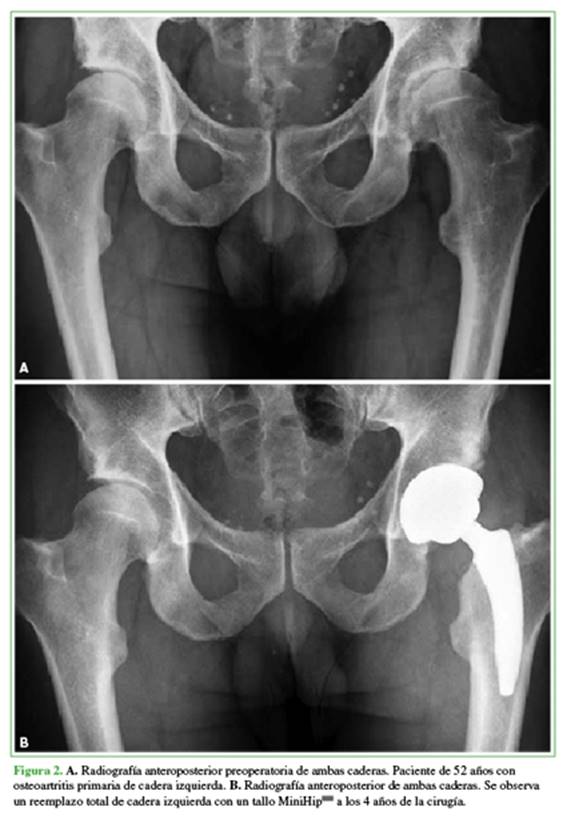

Desde el punto de vista demográfico, es de preferencia su implantación en pacientes jóvenes (≤55 años), aunque en una menor proporción (15%), pueden ser empleados en pacientes de entre 55 y 60 años que practiquen deportes de manera recreativa (Figura 2A y B). Es un requisito que este grupo de pacientes tenga un capital óseo metafisario adecuado junto con un cuello femoral intacto, un calcar morfológicamente normal y una cortical femoral lateral distal suficiente para lograr una correcta fijación y la restauración anatómica.

Las contraindicaciones para el uso de vástagos cortos en cirugía primaria de cadera incluyen la edad >60 años, una deformidad traslacional metafisaria severa del fémur, osteoporosis severa o patologías en las que exista una importante discordancia entre el tamaño del cuello y la metáfisis femoral, por ejemplo, en una osteocondromatosis múltiple (Figura 3).